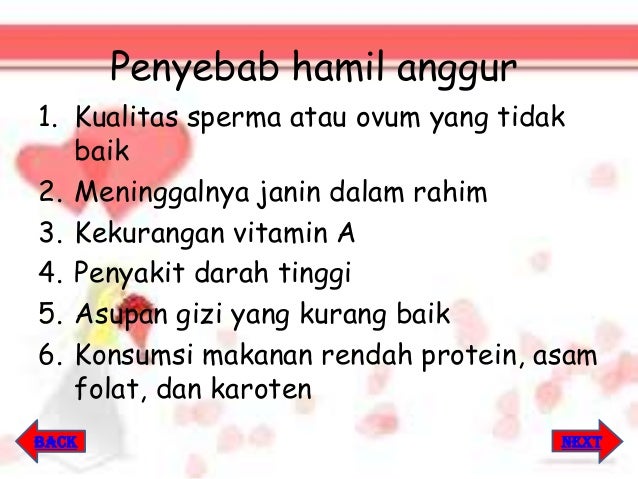

Kuliah Mahasiswa Kehamilan Anggur Mola Hidatidosa Youtube

Kuliah Mahasiswa Kehamilan Anggur Mola Hidatidosa Youtube